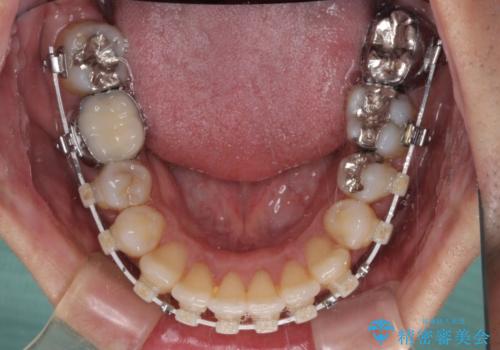

受け口傾向の咬み合わせ 前歯のデコボコをワイヤー矯正で素早く改善

- 審美装置

ワイヤー矯正でもマウスピース矯正でも対応可能とお伝えし、非常に悩まれていましたが、2年後に転勤の可能性が高いとのことで、治療終了までの期間を想定しやすいワイヤー矯正にて治療を行うこととしました。

前歯のクロスバイトは、改善の途中で歯髄壊死を起こすリスクが高くなるため、マウスピース矯正よりもワイヤー矯正をお勧めしております。

この患者様もクロスバイトはあっという間に改善され、1年強で速やかに治療を終えることができました。